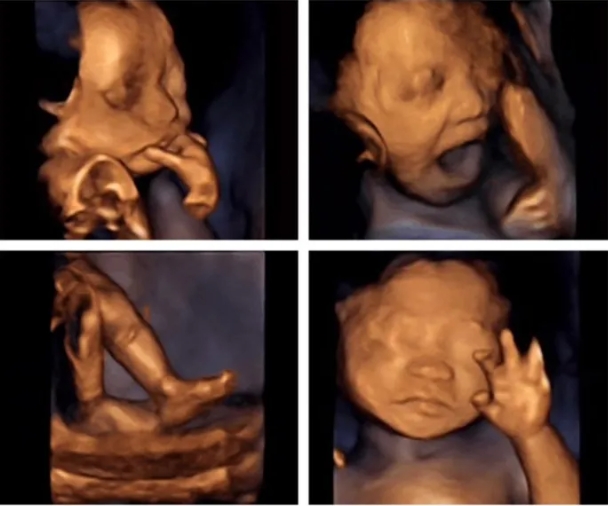

胎儿心脏彩超是胎儿心脏产前超声初步检查,主要采用超声成像技术及彩色多普勒血流成像技术,观察胎儿心脏的大体形态结构,以便对大部分胎儿先天性心血管结构畸形进行可靠的产前筛查和评估。

目前,妇产科超声学会已对产前心脏畸形的超声筛查作了规范基本项目包括:心脏位置、心率、心律、四腔心观、左室流出道及右室流出道。而针对高危胎儿的心脏彩超,在上述检查内容上再增加三血管平面,主动脉弓及导管弓平面等,可对心脏畸形做到早发现、早诊断、早治疗。